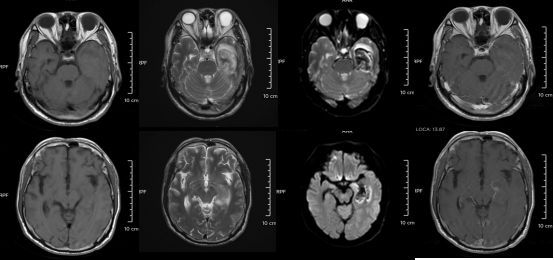

△某单纯疱疹病毒性脑炎患者的医学影像。图源:浙江大学医学院附属第二医院

但如果拖延治疗,甚至会引发脑炎,可能出现癫痫、肢体偏瘫、尿潴留、认知功能障碍等严重后遗症,恢复时间长达3-6个月,甚至影响终身。